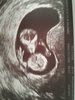

CudownościMój Bejbik to prawdopodobnie chłopiec

Ma już 5,25cmi z 11+2 wskoczył w 12tc

Będzie energiczny bo wierzgał jak szalony

No i dziś usłyszeliśmy jak bije mu serduszko <3

Normalnie aż się poryczałam

Zobacz załącznik 840223